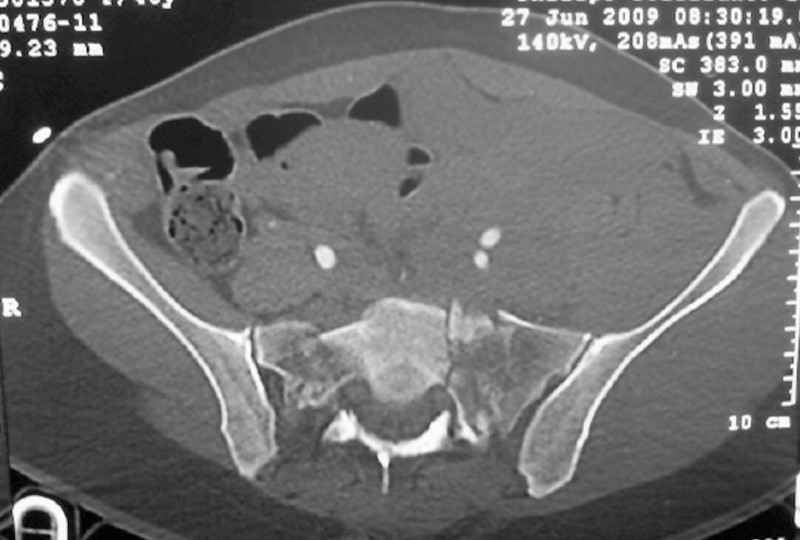

The soft tissues are also in mild condition, buttock hematoma and probably a Morel-Lavalle. I send some more CT images. There are some conminution in the posterior column (I don’t have images now). The patient is scheduled for surgery next Monday. The plan is percutaneous sacral fixation and then ilioinguinal approach .

This complex and displaced sacral injury is likely an H pattern...2 hemipelvic components, an upper sacral component which remains attached to the lumbar spine, and a caudal sacral component...there are typically anterior ring injuries as well...in this patient's example, the left sided acetabulum also has been exploded.

The hemipelvic components' displacements depend on their instability...this patient's left side seems to be the worst.